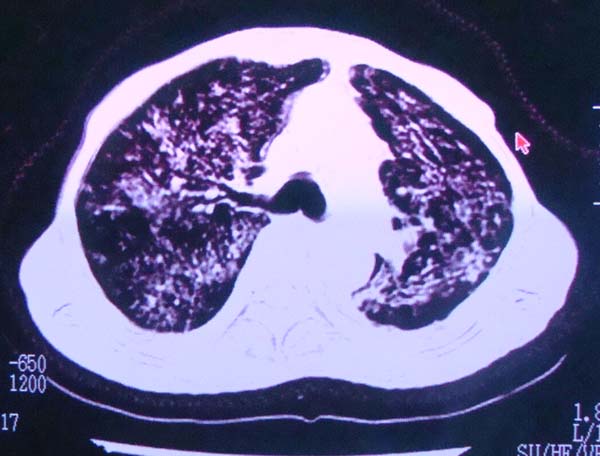

以下是引用zhangzhongshou在2008-2-15 22:25:00的发言:[br]片子照得不清,基本考虑1、细支气管肺泡癌2、亚急性血行播散型肺结核。请结合临床。片子细节显示不清,无法提供进一步意见。

以下是引用杀毒软件在2008-2-15 22:34:00的发言:[br]小叶中心性肺气肿。两肺弥漫性病变,肺泡微石病,过敏性肺炎,尘肺2期,特发性肺纤维化都有可能。[br]不象肺泡癌。